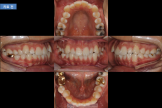

송곳니 덧니, 아랫니 덧니 (20대 여성)

송곳니 덧니와 울퉁불퉁한 아랫니 때문에 교정치료를 받으셨습니다. 가지런하게 배열된 치아를 보실 수 있습니다. 당신의 미소를 생각합니다, 교정전문 서울바른이치과